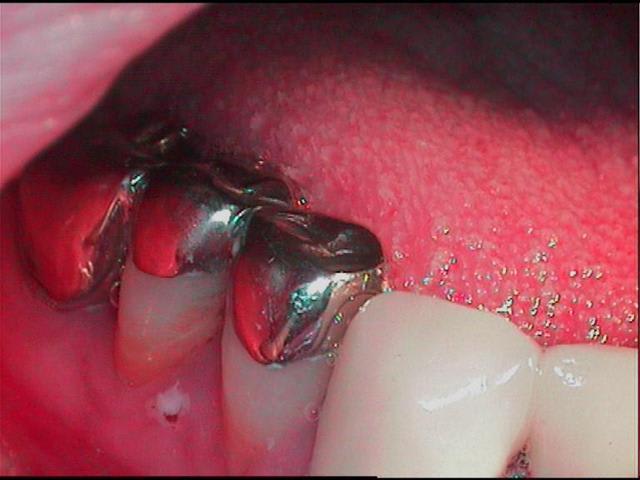

Occl initial hcvx7i - Eugenol

j'ai eu un peu le meme genre de cas adressé, mais plus simple que le tien. j'étais un peu bridé pour le traitement a cause d'un bridge quasi complet en haut

en une fois: non, sur 6mois, le patient a très bien accepté le ttt, mais je dois avouer qu'il avait déjà été très préparé par le confrère ortho qui me l'avait adressé, psychologiquement il était demandeur...physiologiquement j'ai été très progressif pour la dvo, mettant à profit ce temps là pour résorber les granulomes multiples sur les incisives...

moi j'ai utilisé des inlay-onlay en resine auto que je retouchais régulièrement (c'est ringard et galère, meme tres galere)